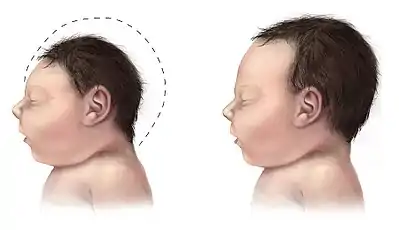

| A baby with microcephaly (left) compared to a baby with a typical head size | |

There are a variety of symptoms that can occur in children. Infants with microcephaly are born with either a normal or reduced head size.[10] Subsequently, the head fails to grow, while the face continues to develop at a normal rate, producing a child with a small head and a receding forehead, and a loose, often wrinkled scalp.[11] As the child grows older, the smallness of the skull becomes more obvious, although the entire body also is often underweight and dwarfed.[10]